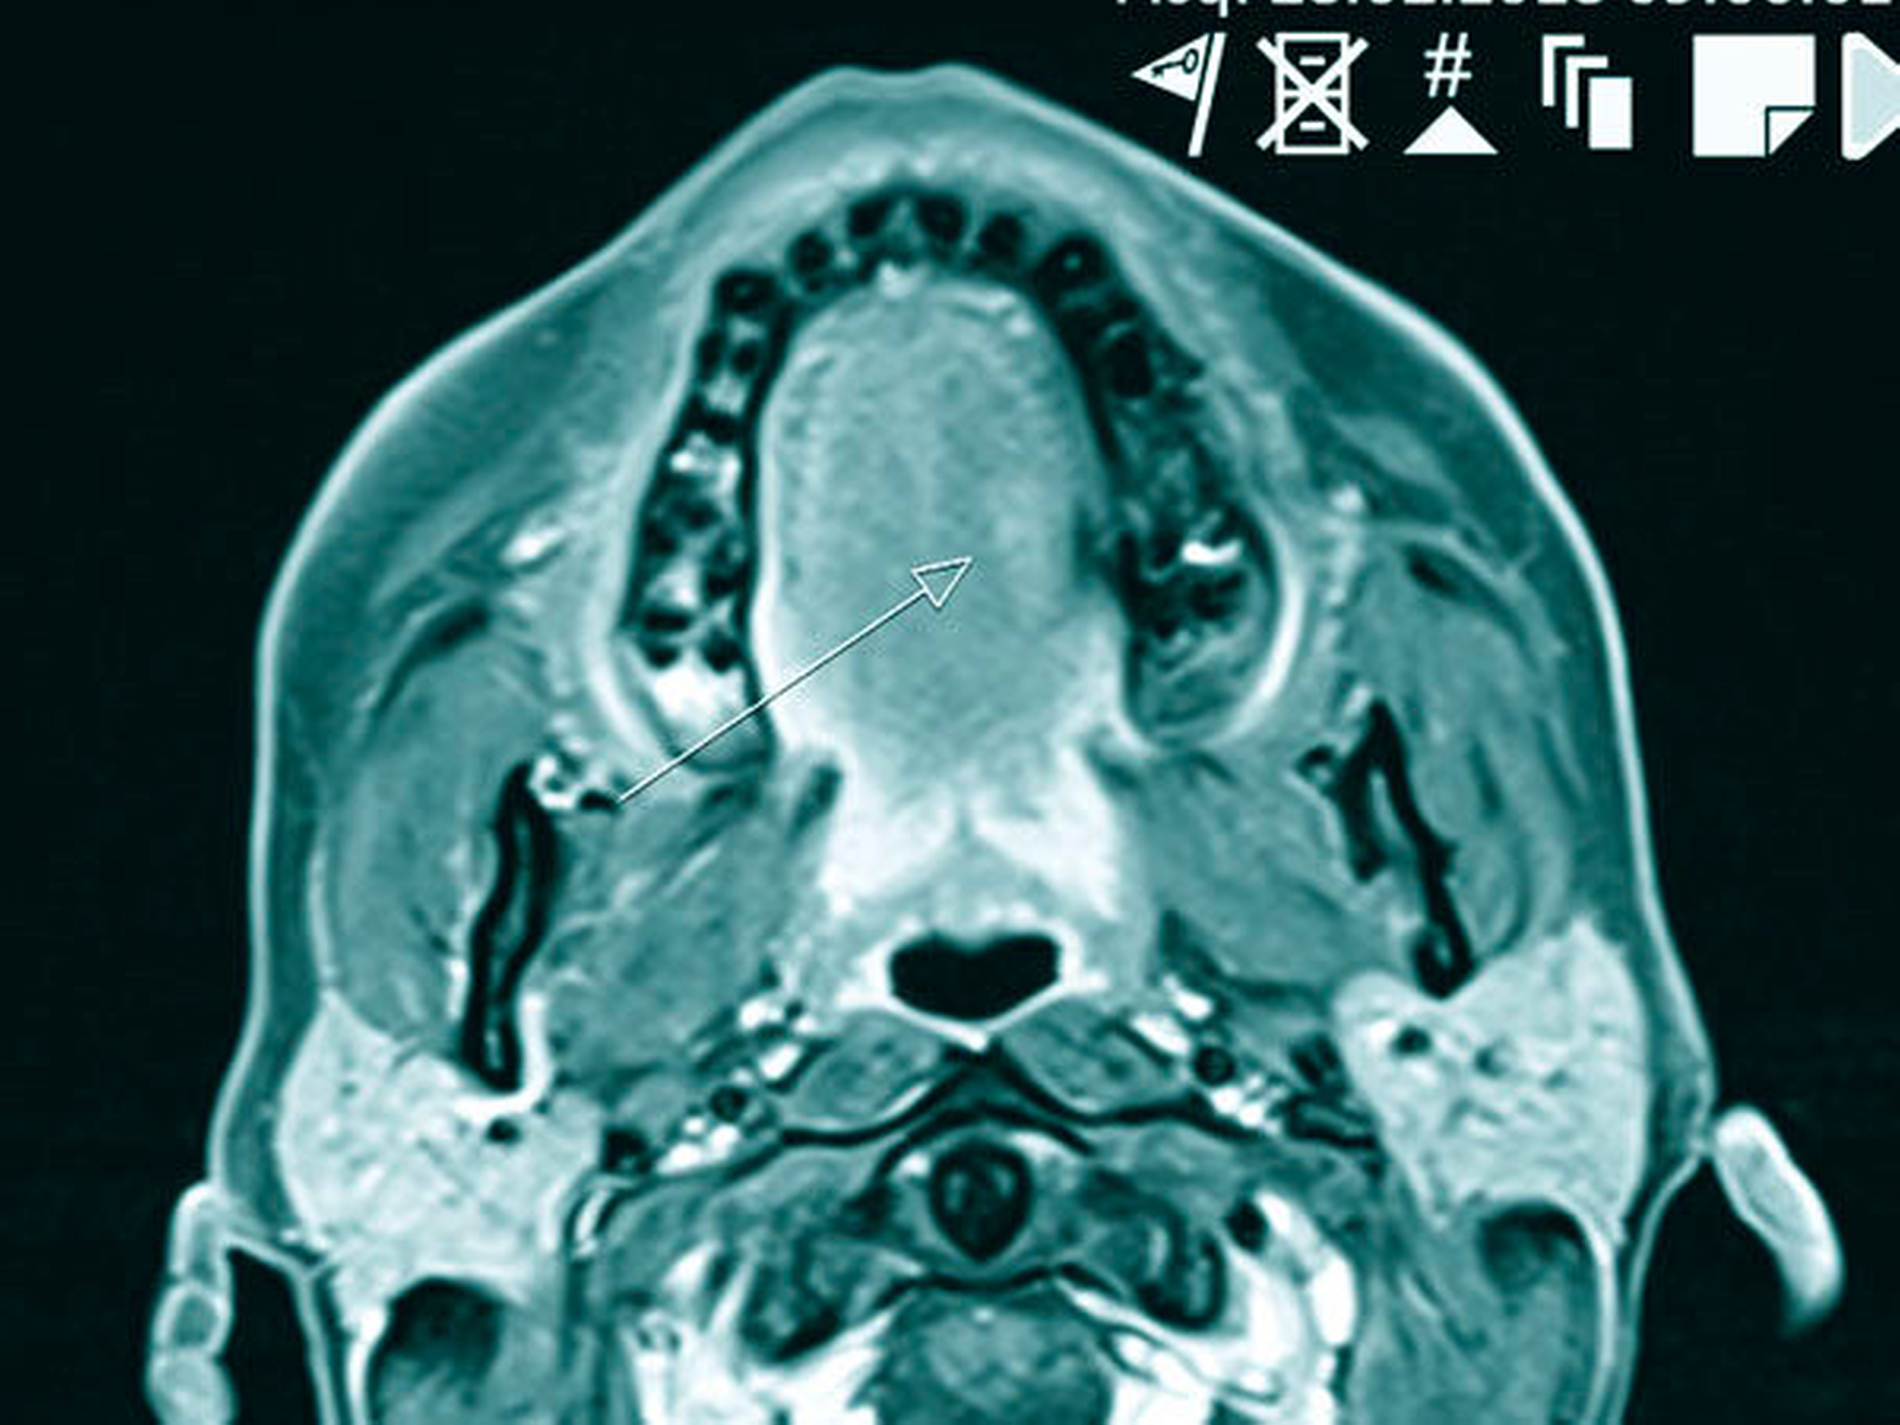

Die vom Hausarzt überwiesene Patientin stellte sich mit einer knotigen Struktur unterhalb der unversehrten Zungenmukosa des linken mittleren Zungenrückens vor (Abbildung 1). Der Knoten war derb palpabel, nicht verschieblich und weder in Ruhe noch auf Druck dolent. Bis auf den erhabenen Aspekt beschrieb sie keinerlei Beschwerden. Im MRT stellte sich in Projektion auf die linke Zunge submukös eine vorwiegend unscharf begrenzte, etwa 10 mm x 8 mm messende, Kontrastmittel-aufnehmende Struktur dar. Es gab keinen Anhalt für weitere Raumforderungen oder Lymphknotenvergrößerungen (Abbildungen 2 und 3). Da von einem benignen Tumor ausgegangen wurde, erfolgte im Rahmen einer kurzen Intubationsnarkose die In-toto-Exzisionsbiopsie mit knappem Sicherheitsabstand. Der intraoperative Situs zeigte, wie schon nach der initialen Bildgebung vermutet, eine unscharf begrenzte, solide, in die Zungenmuskulatur hineinreichende Raumforderung mit weißlich-gelblicher Färbung der Schnittfläche (Abbildungen 4 und 5). Nach Resektion und ausgiebiger Blutstillung konnte die Wunde primär mit resorbierbaren Fäden verschlossen werden (Abbildung 6).